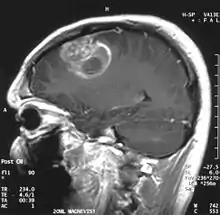

Diagnóstico

Quando visto através da ressonância magnética, os glioblastomas frequentemente aparecem como lesões com realce em anel. No entanto, esta aparência não é específica, já que outras lesões como abscessos, metástases e esclerose múltipla tumefativa podem ter uma aparência similar.[12]

O diagnóstico definitivo do glioblastoma multiforme requer uma biópsia estereotática ou uma craniotomia com ressecção do tumor e confirmação patológica.